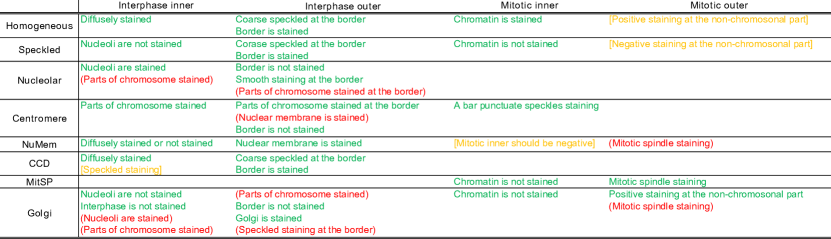

Each specimen image contains a collection of interphase and mitotic cells which are important for the specimen-level classification (refer to Fig. 2). The mitotic cells are the HEp-2 cells undergoing the mitosis phase. In this phase each cell divides itself into two separate individual cells. The mitotic cells are of importance as they produce a set of antigens which are either less concentrated or undetectable in the interphase stage. Due to this fact, experts consider the pattern of both interphase and mitotic cells in classifying an ANA specimen.

4.4 Describing ANA pattern class

In this section we use the attributes discovered by the proposed approaches to generate a textual description of the eight ANA patterns. To that end, we use attributes trained by CRAD as it gives the most consistent results in the previous evaluation. Specifically, we opt to use 32 attributes extracted from inner and outer regions from both cell types.

We first selected the most frequently appearing cell-level attributes from each pattern. From the selected set, we further excluded the attributes which appear in at least more than four classes. Finally, to name the cell attributes, we presented each cell attribute to the domain experts who were trained to read ANA by showing them both images classified as positive and negative by the attribute classifier. We note that we presented the cell images in green colour which is similar to the colour of an ANA specimen under a fluorescent microscope. Since the attributes are extracted from each cell region, we could ask more specific questions to the experts in relation to each region (e.g. Please describe the property appearing at the cell boundary). The experts could opt not to name an attribute if they were not able to find any consistent property in the positive cell images. Fig. 5 and 1 present some examples of cell attributes successfully identified by the experts.

Once the description for each class was generated, we let the experts indicate the correctness of each text description. Fig. 6 presents the generated description of each pattern. Most patterns could be reasonably described with minor errors or omissions in the description. The mitotic spindle pattern was perfectly described with no errors or omissions in the description. On the other hand, despite this system being able to detect the important property of Golgi (i.e. golgi organelle is stained), the system had more mistakes on Golgi than the other patterns. This is probably due to the fact that the Golgi pattern has only one prominent property.